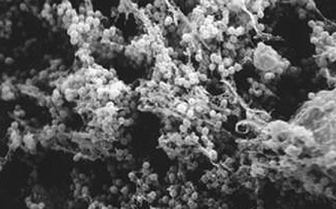

バイオフィルムとは、細菌によって作られたスライムと呼ばれる

長時間使用していると、ケース内にはこうしたバイオフィルムに守られた細菌の巣がたくさんできます。煮沸消毒なら死滅させることも可能ですが、近ごろ頻用されているマルチパーパス・ソリューションではなかなか歯が立ちません。ケース内をいつもきれいにしておくとともに、新しいケースと定期的に交換する必要があります。

バイオフィルム